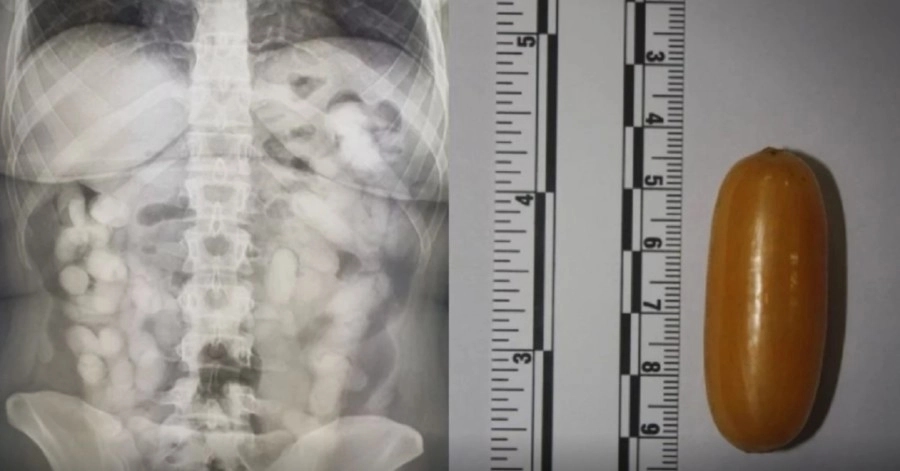

Nju su izdvojili od ostalih putnika, a pregledom je utvrđeno prisustvo droge na prtljagu. Nakon toga je upućena na rendgensko snimanje kojim je utvrđeno da u tijelu ima 76 stranih tijela, tj. kapsula.

Ono što je zanimljivo je to da je Andrei trebalo punih 10 dana da iz tijela “izbaci” kapsule s drogom, uprkos tome što je uzimala jake laksative. Nakon deset dana utvrđeno je da je ona u tijelu imala ukupno 990 grama kokaina.